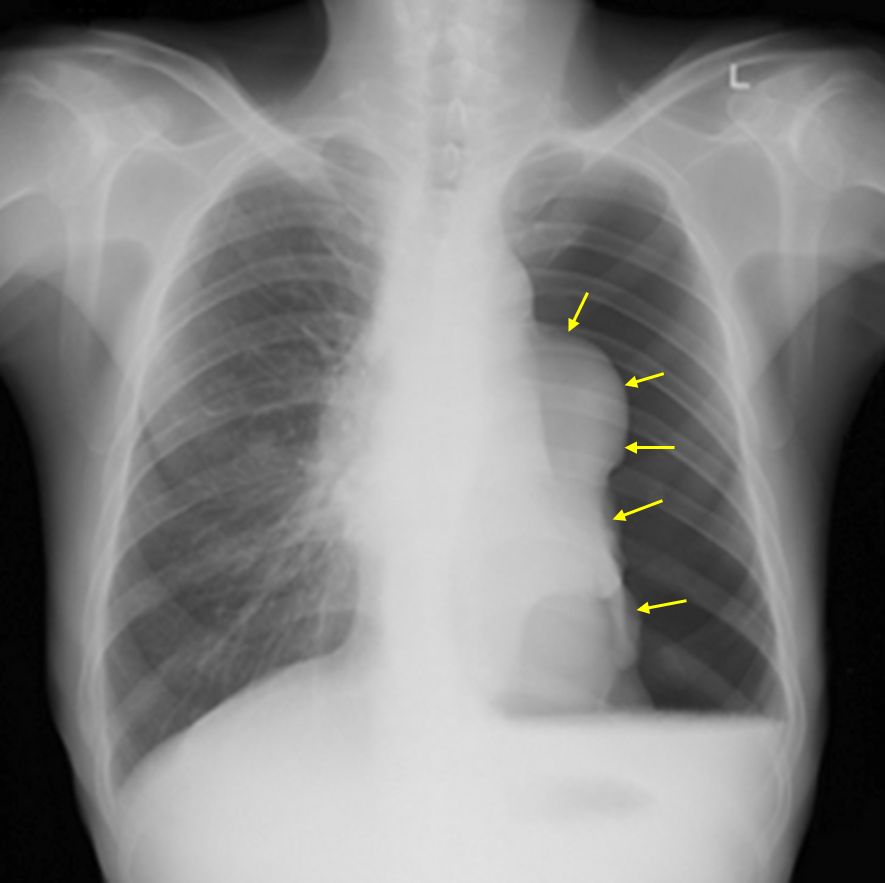

69세 남자가 2시간 전부터 갑자기 왼쪽 가슴 통증과 함께 숨이 찬다며 병원에 왔다. 50갑 ∙ 년의 흡연자이다. 혈압 110/70 mmHg, 맥박 90회/분, 호흡 26회/분, 체온 36.5℃이다. 가슴 청진 시 왼쪽 가슴에서 호흡음이 거의 들리지 않고 타진하면 기체팽만음이 들린다. 가슴 X선사진이다. 치료는?

Img | CXR: Large amount of pneumothorax at Lt. chest cavity, Lt. lung total collapse, with air-fluid level |

• CXR상 좌측 폐혈관 음영이 전혀 보이지 않으므로 매우 큰 크기의 기흉이 있음을 알 수 있으며, 좌측 폐는 완전히 collapse된 것으로 보인다. 또한 좌측 흉강에 air-fluid level이 있으므로 흉막 삼출이 합병되었다고 볼 수 있다.

• 고령과 흡연력을 고려할 때 COPD 등에 의해 SSP가 발생했다고 추정할 수 있다. SSP의 1st line 치료는 흉관 삽입이며, 현재 pleural effusion이 동반되었으므로 더욱 흉관 삽입을 시행해야 한다.